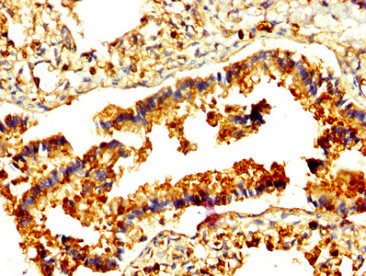

IHC image of CSB-PA019305LA01HU diluted at 1:500 and staining in paraffin-embedded human lung tissue performed on a Leica BondTM system. After dewaxing and hydration, antigen retrieval was mediated by high pressure in a citrate buffer (pH 6.0). Section was blocked with 10% normal goat serum 30min at RT. Then primary antibody (1% BSA) was incubated at 4°C overnight. The primary is detected by a biotinylated secondary antibody and visualized using an HRP conjugated SP system.